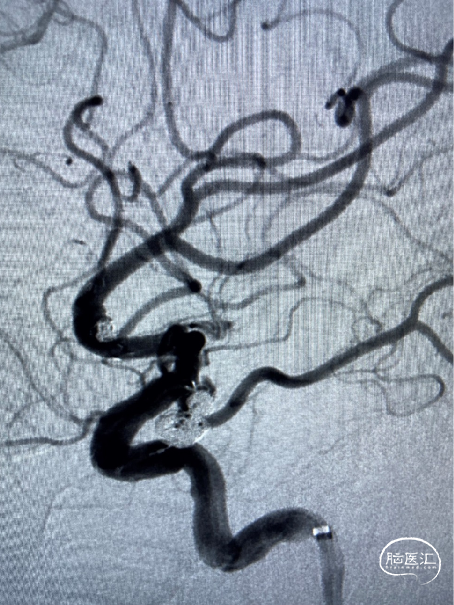

术 后

![]()

替罗非班6ml/h持续泵入24小时后桥接双抗.

2022-2-12头颅CT复查:左侧基底节区腔隙灶、脑白质变性、脑萎缩、左额叶斑点状高密度影无著变,鞍区术后改变。